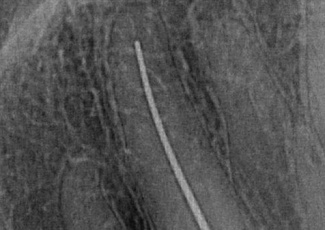

Лікування проводилося під анестезією та з використанням кофердаму. Під мікроскопом було зроблено мінімально інвазійний ендодонтичний доступ до кореневого каналу. Виявлено, що вітальність пульпи в перших двох третинах каналу була відсутня. Канал відпрепаровано ротаційними машинними та ручними нікель-титановими інструментами на робочу довжину 31 мм. Визначення довжини каналу було проведене модифікованим ручним K-FILE №15.